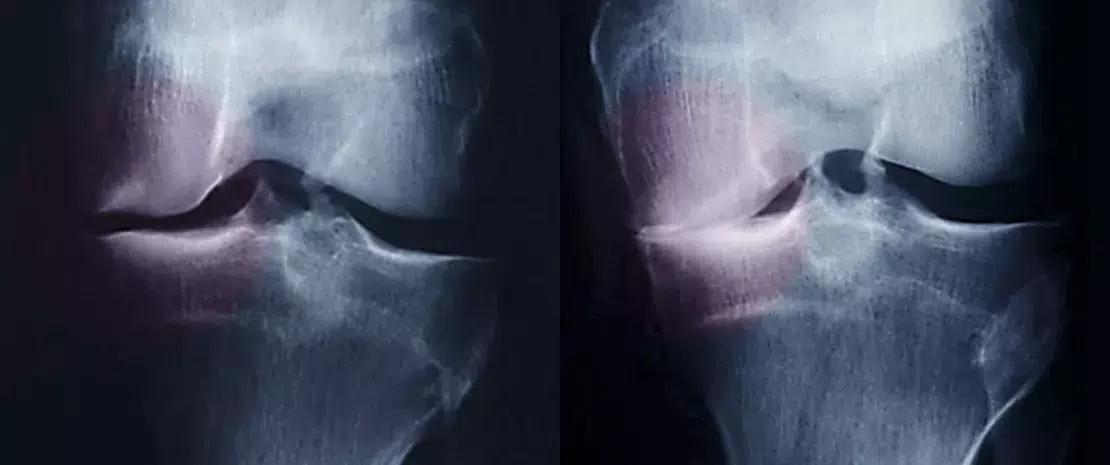

As pessoas com excesso de peso, devido à sobrecarga nas articulações, têm maior propensão para contraírem artrose. Mas como é que se poderá detetar os pacientes mais expostos a esse risco? Talvez através da sua microbiota intestinal, que tem uma participação em muitas doenças inflamatórias, incluindo a artrose.